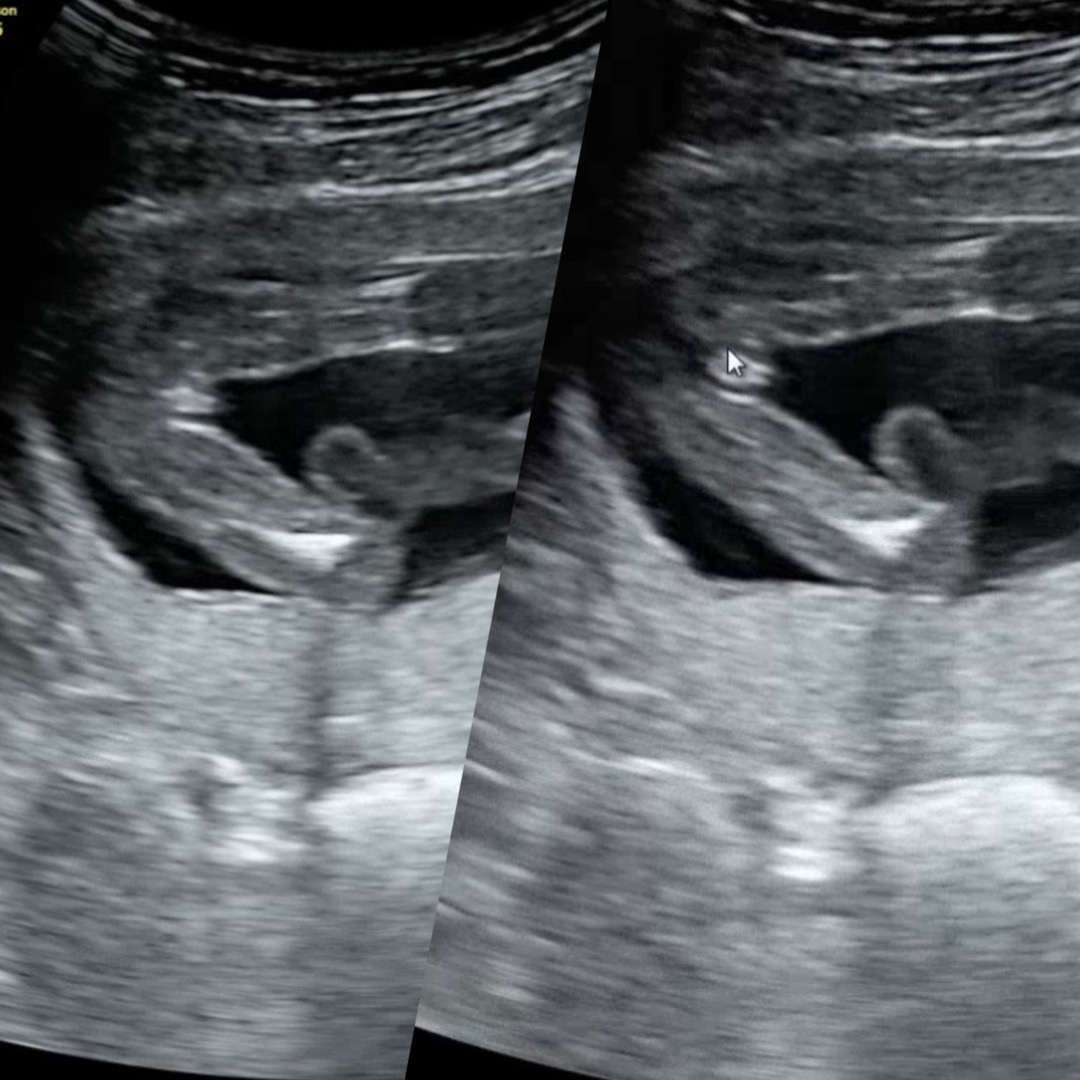

16주차 딸이라고 하시는데 꼬추가 보여요

16주차 검진 다녀오면서 의사선생님이 딸이라고 딱 집어서 말해주셨는데 집에와서 마미톡 보니 아무리 봐도 작긴 하지만 고추 같은 게 있어요 아들확정 받은 분들 보면 더 크긴 하던데.. 선생님이 이걸 모르실리 없어서 딸이겠지? 하다가도 사진 보면 모양이 참 고추 같네요.. 이게 더 들어가는 건지 ㅎㅎ..12주차 검진 땐 티끝없이 아무것도 없었는데 신기하네용

저도 딸인데 저런식으로 보여서 선생님한테 저건뭐에요..? 라고 여쭈어보니 탯줄이에요~라고 하셨어욥 !아들 초음파는 보면 존재감이 뿜뿜하더라구여

앗 정말요 굵은 탯줄이 옆에 보이길래 생각도 못했네요😂저는 고추인데 작은건가?..했어요 ㅎㅎㅎ..